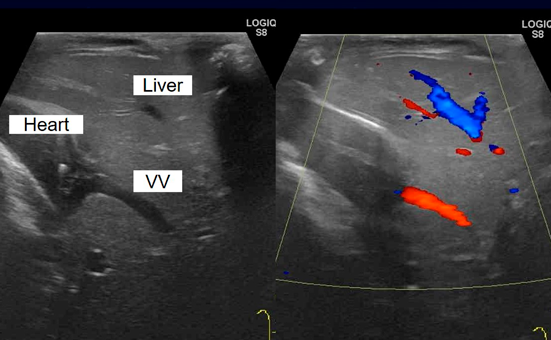

Fig. 4 Postoperative cardiac catheterization showed a portosystemic shunt draining from the portal vein to the left-sided atrium via the left unligated vertical vein (VV)

VV, vertical vein.

PSSに関して,血液検査において肝逸脱酵素,アンモニア,血糖,および凝固系のいずれも正常範囲内で経過したが,心エコーで左側房室弁逆流を軽度認めた.術後5か月,8か月時に施行した心臓カテーテル検査では,肺血管抵抗1.3–2.1単位・m2と良好であったが,心房圧10–11 mmHgと軽度上昇を認め,PSSによる容量負荷の可能性が考えられた.遺残垂直静脈を閉鎖する方針として,遺残垂直静脈(Fig. 4)の閉塞試験を行ったところ門脈圧は20 mmHgと許容内であった.1歳1か月時に開腹下で遺残垂直静脈の結紮術を試みたが,結紮の際に腸管鬱血を認めたため遺残垂直静脈の絞扼のみに留めた.心臓に関しては,右下肺静脈狭窄が徐々に進行し,経皮的バルーン血管形成術および外科的肺静脈解除術を経て,2歳時に両方向性Glenn手術を施行した.この術後経過の中でPSSの症状や血液検査所見の異常は認めなかった.